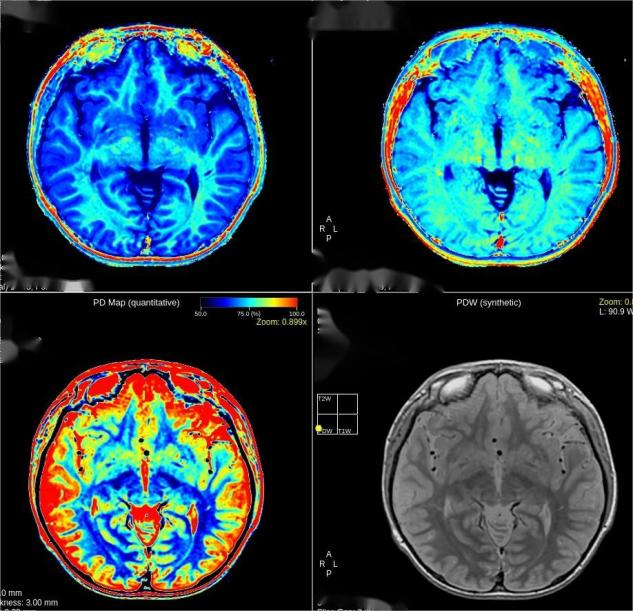

今年7月5日,3.0T磁共振设备正式投入临床及科研工作至今,多位患者从中受益。设备具备高清弥散、MAGIC(一种一站式弛豫定量技术,一次扫描获多组不同对比度图像和多种弛豫定量数据)、全脑静音血管成像、骨关节成像、四维流心血管磁共振成像(4D FlowCMR)、压缩感知等技术。

和普通磁共振相比,它的分辨率和信噪比明显提高,能够带来更高的图像质量,从而更早发现微小病变。

3.0T磁共振设备检查成像分辨率和信噪比明显提高,可更早发现微小病变。